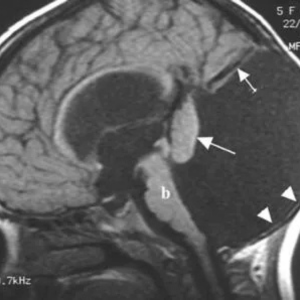

Hydrocephalus